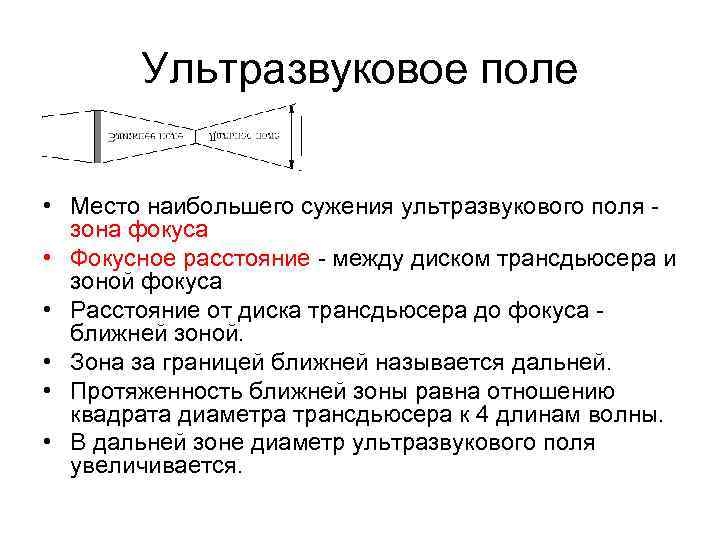

Ультразвуковое поле • Место наибольшего сужения ультразвукового поля - зона фокуса • Фокусное расстояние - между диском трансдьюсера и зоной фокуса • Расстояние от диска трансдьюсера до фокуса - ближней зоной. • Зона за границей ближней называется дальней. • Протяженность ближней зоны равна отношению квадрата диаметра трансдьюсера к 4 длинам волны. • В дальней зоне диаметр ультразвукового поля увеличивается.

Ультразвуковое поле • Место наибольшего сужения ультразвукового поля - зона фокуса • Фокусное расстояние - между диском трансдьюсера и зоной фокуса • Расстояние от диска трансдьюсера до фокуса - ближней зоной. • Зона за границей ближней называется дальней. • Протяженность ближней зоны равна отношению квадрата диаметра трансдьюсера к 4 длинам волны. • В дальней зоне диаметр ультразвукового поля увеличивается.